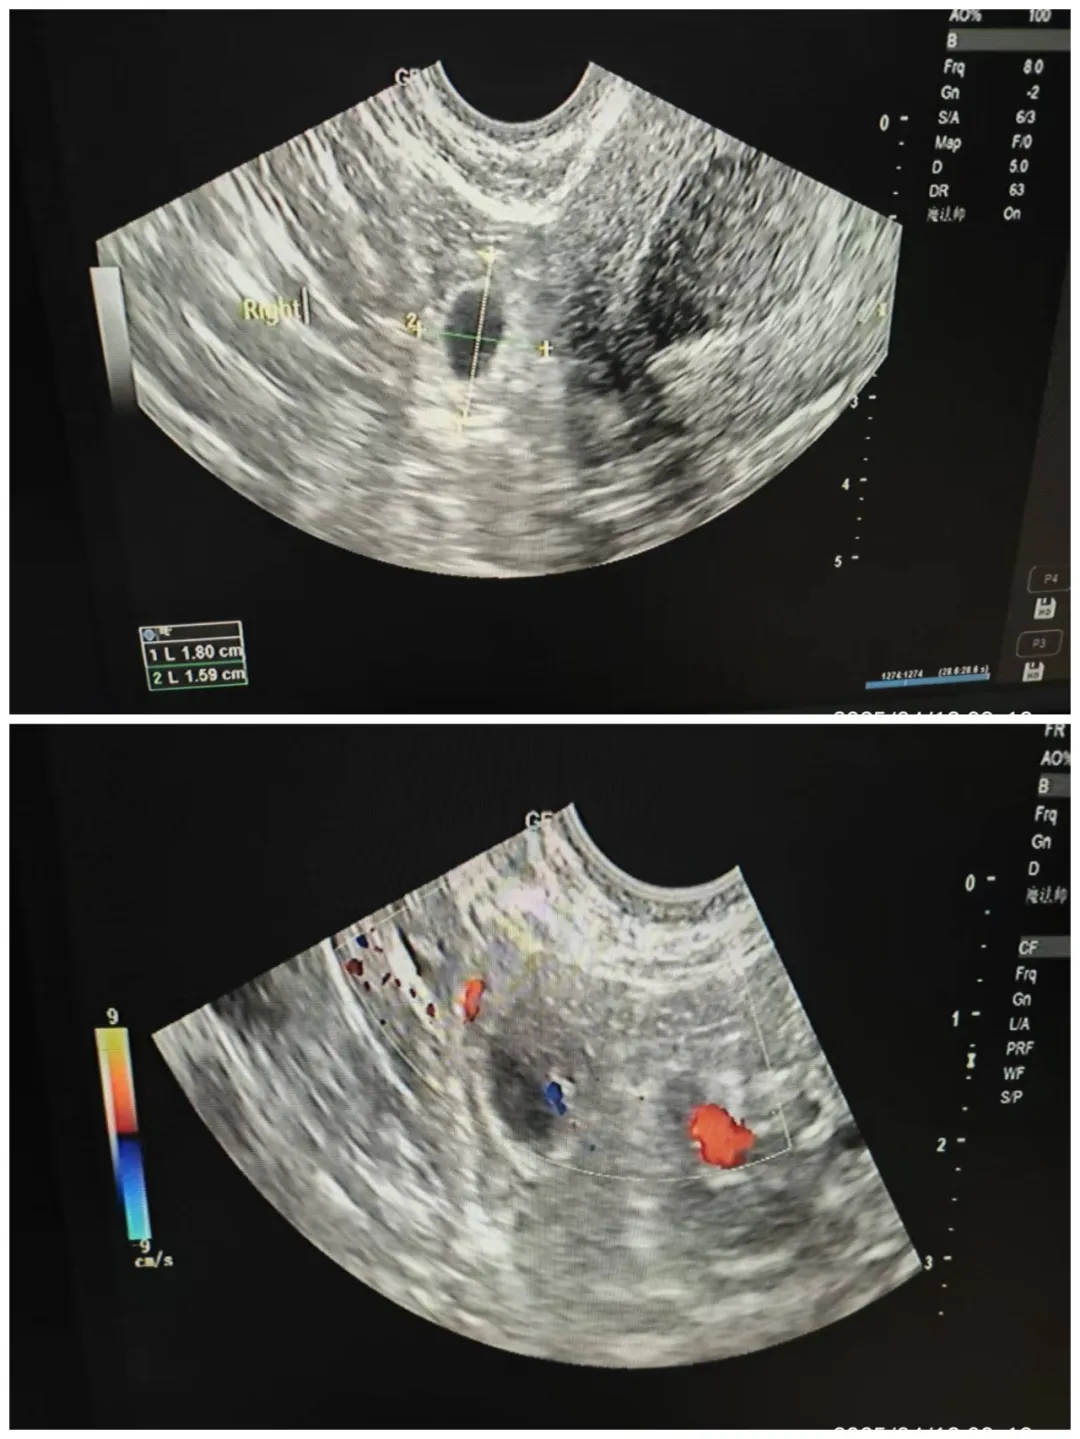

检查过程中,医生们如侦探般抽丝剥茧,在错综复杂的影像中发现关键线索:子宫虽外形饱满、肌层回声均匀,但宫腔内出现约4.3x2.1cm的不规则无回声区域,节育器强回声位置偏移;宫颈处可见直径约0.6cm的囊性结节;而右侧卵巢上方的1.8x1.6cm混合回声包块更是“暗藏玄机”,其中1.5x1.4cm的囊性回声内,卵黄囊、直径约0.3cm的胎芽组织以及心管搏动清晰可见。凭借深厚的专业知识与丰富的临床经验,功能科团队当即做出精准判断——宫外孕(右侧),同时提示宫腔积血合并节育器嵌顿。